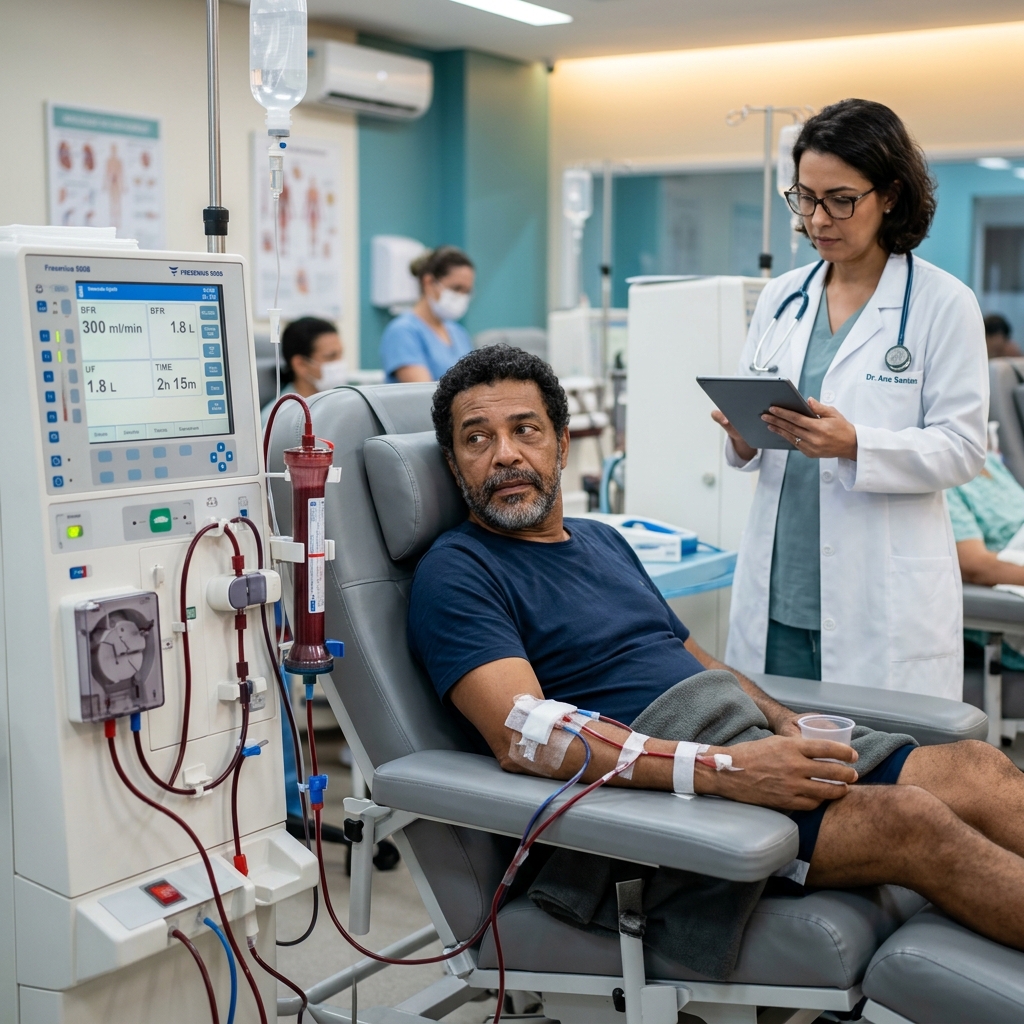

Descubra como a hemodiálise e diálise peritoneal substituem a função renal e mantêm a vida.

Entenda como funciona a máquina, o acesso vascular, a rotina das sessões e qualidade de vida.

Entenda em detalhes o processo de filtragem do sangue, o rim artificial e cuidados vitais.